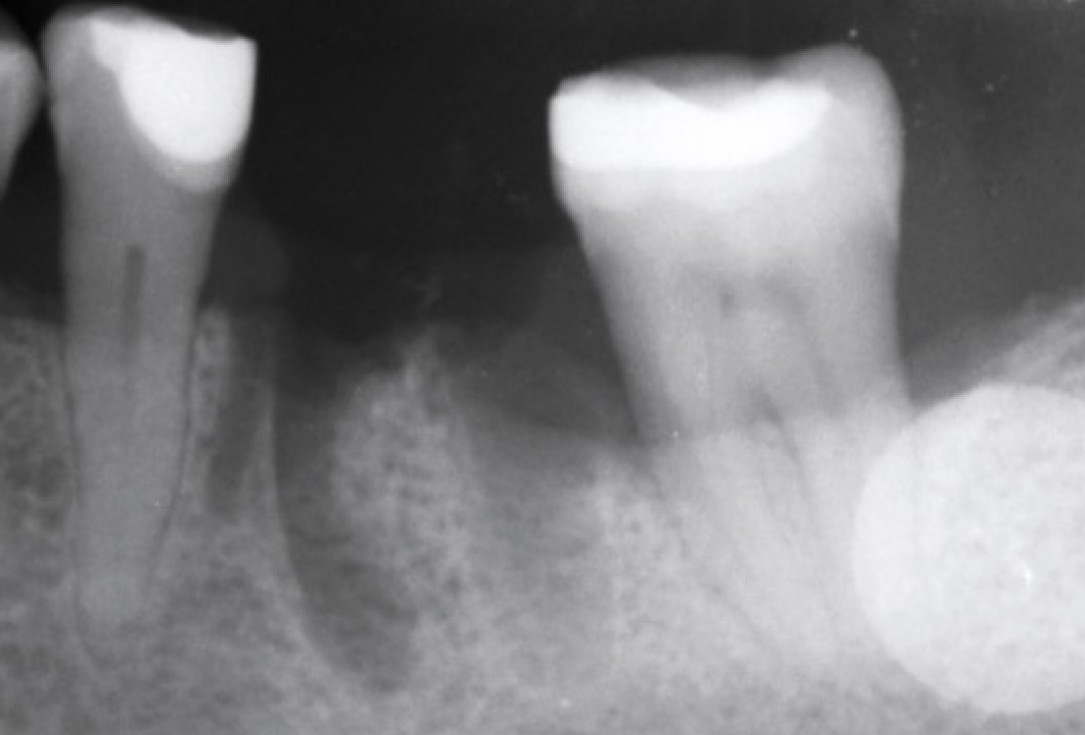

X-ray control before tooth extraction